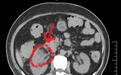

然而,外院及我院常规超声影像检查均没有查出相应病灶,且经过广谱抗生素泰能药物抗感染后患者仍反复发热。面对这种情况,金文胜教授当即决定行腹部CT增强扫描,果然在右肾下极腹侧靠近内侧的皮质包膜下有可疑蜂窝状并囊性感染灶,这个位置的脓肿非常罕见,也是超声检查的死角。